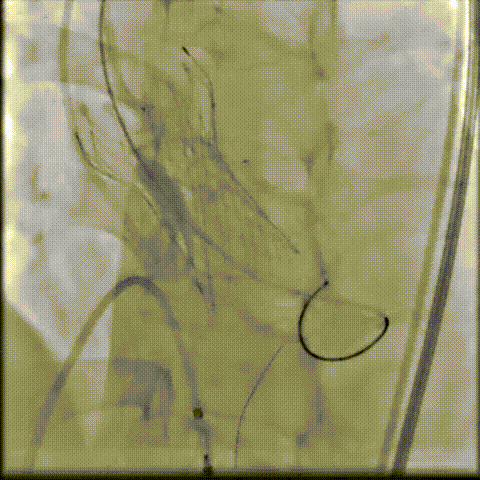

术中影像

根部造影可见返流;20mm球囊预扩,LCA灌注缝隙狭小

预置LCA保护;第一次释放,

团状钙化挤压导致瓣膜(AV23)少量下滑

回收后重新定位,第二次释放,

瓣膜(AV23)深度仍未达到最佳预期

完全回收,第三次定位释放,瓣膜(AV23)位置良好

瓣膜工作位释放“烟囱支架”;

瓣膜(AV23)完全释放后,“烟囱支架”后扩

最终造影,“烟囱支架”显影清晰,瓣膜形态及LCA灌注良好